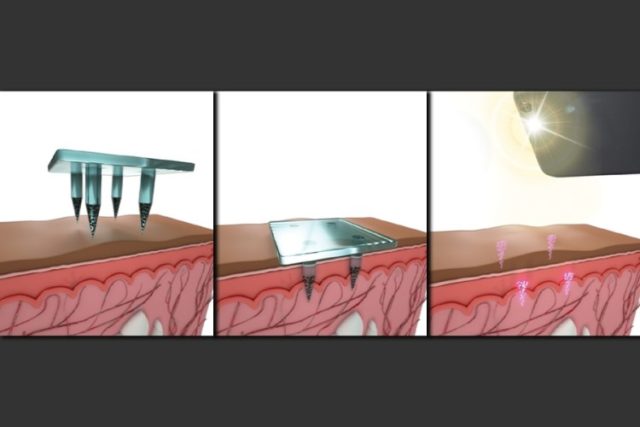

Statt mit einer urtümlichen Spritze bekommt man die Impfung dann per Pflaster in die Haut gedrückt. Die winzigen Nadeln sind aus einer Art löslichem Zucker und einem Polymer (PVA), dem Quantenpunktfarbsoff und sie enthalten den Wirkstoff, der sich mit den Nadeln im feuchten Milieu im Körper auflöst und im Körper verteilt.

Wenn das Pflaster auf die Haut aufgeklebt wird, lösen sich die 1,5 Millimeter langen Mikronadeln teilweise auf und geben ihre Nutzlast innerhalb von etwa zwei Minuten ab. Die kleinen Mikrokristalle lösen sich nicht auf, sondern verbleiben an der Stelle, wie QR-Punkte und können ausgelesen werden. Hier eine Darstellung aus dem Bericht des MIT:

Das Pflaster kann so angepasst werden, dass verschiedene Muster eingeprägt werden können, die der Art des verabreichten Impfstoffs entsprechen. Natürlich bleibt es weder beim Impfen, noch beo der eintätowierten Krankenakte. Robert LAnger sieht wunderbare Möglichkeiten: